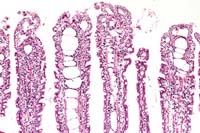

Contributor's Diagnosis and Comments: Acute severe necrotizing bursitis.

Etiology: Birnavirus. Name the Disease: Infectious Bursal Disease (IBD/Gumboro Disease).

The gross findings of dehydration, multiple linear hemorrhages within leg muscles and the swollen edematous bursae of Fabricius are typical of IBD infection.

Case 18-4. Bursa of Fabricius. There is acute necrosis of the lymphoid follicles with an intact surface epithelium and heterophil exudate in the lumen. 10X

AFIP Diagnosis: Bursa of Fabricius: Lymphoid necrosis and depletion, diffuse, severe, with heterophilic bursitis, breed unspecified, chicken, avian.

Conference Note: The cloacal bursa (bursa of Fabricius) appears to be the primary target organ of the virus. Gross lesions observed in the bursa follow a sequence of change over time. On day 3 post-infection (PI), the organ begins to increase in size and weight because of edema and hyperemia. By day 4 PI, it is usually twice its normal weight and size; it then begins to become smaller. It continues to atrophy, and by day 8 PI, it is approximately one-third its original weight.1

IBD virus has an affinity for pre-B lymphocytes. Histologic lesions can be found in all lymphoid organs, but are most severe in the cloacal bursa. By 1-2 days PI, there is degeneration and necrosis of lymphocytes in medullae of bursal follicles. Following cell lysis, large amounts of virus are released from the bursa, producing a secondary viremia. In the bursa, lymphoid cells are soon replaced by heterophils, cellular debris, and hyperplastic reticuloendothelial cells. Hemorrhage may occur. As the inflammatory reaction declines, cystic cavities may develop in follicular medullae.